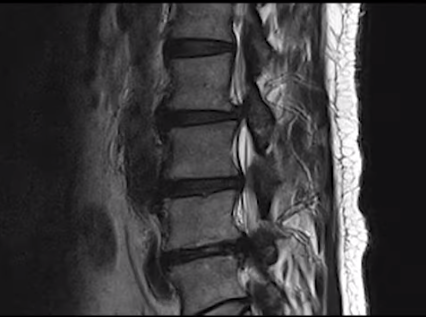

먼저 이 환자분에 대한 치료 전 MRI 상태를 설명 드린 후

환자분의 얘기를 직접 들어보겠습니다.

이 환자분은 협착증을 25년간 앓으시고 증상도 매우 심하신 환자분입니다.

허리 세 마디 2번 3번, 3번 4번, 4번 5번, 이렇게 세 마디의 척추관이 심하게 막혀 있습니다.